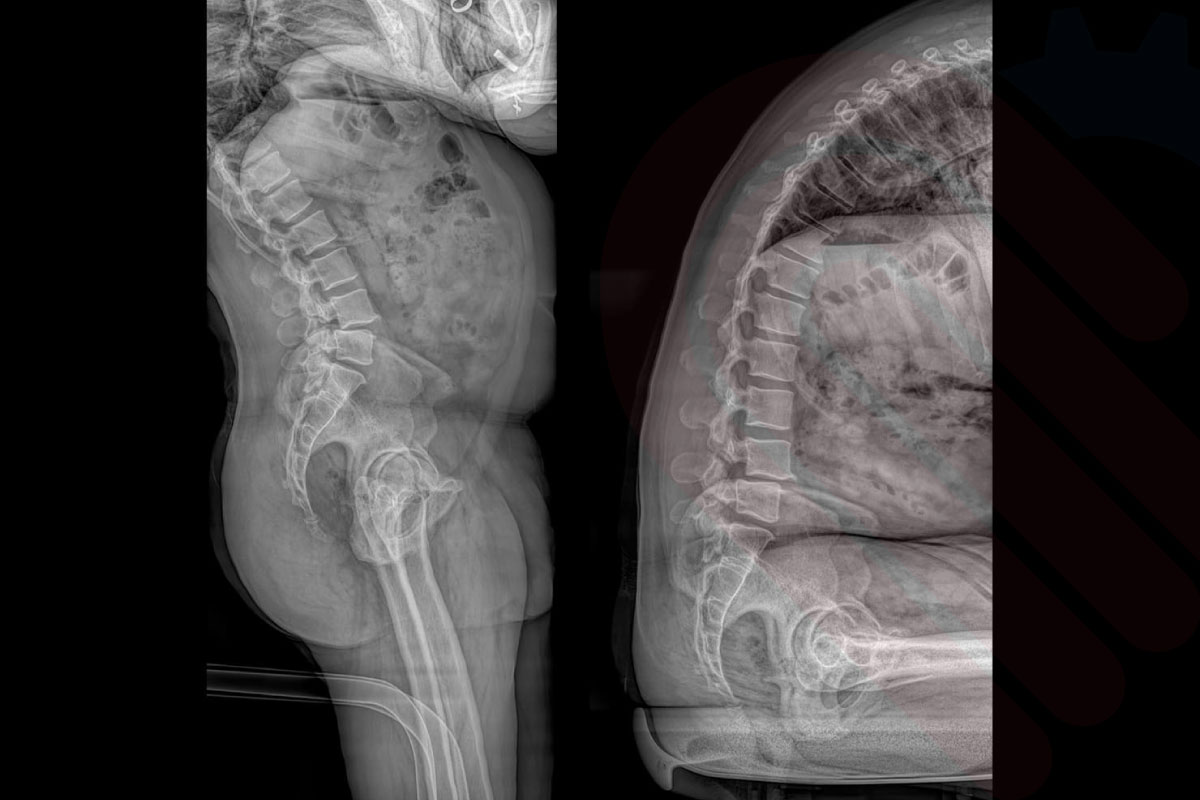

EOSedge®, ortopedi ve kas-iskelet sistemi tanısında yeni bir standart belirleyen, düşük doz radyasyonla yüksek çözünürlüklü biplanar görüntüleme sağlayan gelişmiş bir sistemdir. Skolyoz, kalça-diz deformiteleri, alt ekstremite hizalanma bozuklukları ve travma sonrası değerlendirmelerde; 1:1 oranlı, distorsiyonsuz ve yük taşıyan pozisyonda alınan görüntülerle cerrahlara güvenilir tanı ve cerrahi planlama imkânı sunar.

EOSedge, hastanın başından ayak bileğine kadar tek pozisyonda tam vücut görüntüleme imkânı sunar. Geniş görüş alanı ve dikey tarama teknolojisi sayesinde tüm iskelet yapısı doğal yük taşıma pozisyonunda görüntülenir. Bu, skolyoz, bacak uzunluğu farklılıkları ve eklem hizalanma bozukluklarının değerlendirilmesinde kritik öneme sahiptir.

EOSedge, aynı anda hem önden (AP) hem de yandan (lateral) yüksek çözünürlüklü görüntüler alabilen biplanar görüntüleme teknolojisine sahiptir. Bu sayede, hasta tek bir pozisyonda dururken iki farklı perspektiften tam iskelet görüntüsü elde edilir. Biplanar yapı, anatomik detayların doğru şekilde değerlendirilmesini sağlar ve cerrahi planlamalarda yüksek doğruluk sunar.

EOSedge, hastaların tarama sırasında doğal ve rahat bir pozisyonda durabilmesi için özel olarak tasarlanmıştır. Dikey ve yatay eksende ayarlanabilir sistem yapısı, hem pediatrik hem yetişkin hastaların en doğru pozisyonda hizalanmasını sağlar. Oturma ve ayakta durma pozisyonları sayesinde skolyoz, diz eklem dejenerasyonu veya kalça displazisi gibi durumlar fizyolojik duruş bozulmadan görüntülenebilir. Ergonomik tasarım, özellikle hareket kısıtlılığı olan hastalarda tarama sürecini kolaylaştırır ve hasta uyumunu artırır*.

spineEOS, EOSedge ile elde edilen düşük doz biplanar görüntüleri kullanarak omurga deformitelerinin 3D planlamasını sağlayan ileri düzey bir yazılımdır. Cerrahlar, hasta ayakta veya oturur pozisyonda iken alınan gerçek boyutlu görüntüler üzerinden, sagittal ve koronal düzlem analizlerini yapabilir, tedavi sonrası beklenen omurga hizalanmasını simüle edebilir. Özellikle skolyoz ve kifoz cerrahilerinde, implant yerleşim açılarından segmental hizalanmaya kadar çok sayıda parametreyi önceden değerlendirme imkânı sunar. Klinik çalışmalar, spineEOS kullanılarak yapılan preoperatif planlamaların, cerrahi sonrası hizalanma doğruluğunu anlamlı ölçüde artırdığını göstermektedir*.

hipEOS, EOSedge sistemi ile elde edilen düşük doz, gerçek boyutlu biplanar görüntüler üzerinden kalça ekleminin 3D analizini ve cerrahi planlamasını yapan gelişmiş bir yazılımdır. Total kalça protezi (THA) ve diğer kalça rekonstrüksiyon cerrahilerinde, asetabular kupa açısı, femoral stem pozisyonu, bacak uzunluğu farkı ve offset gibi kritik parametreleri preoperatif olarak belirlemenize olanak tanır. Yük taşıyan pozisyonda elde edilen görüntüler sayesinde, implant yerleşimi ve pozisyonlaması hastanın doğal biyomekaniğine en uygun şekilde planlanabilir. Klinik veriler, hipEOS planlaması ile gerçekleştirilen operasyonlarda postoperatif bacak uzunluğu eşitliği ve komponent pozisyon doğruluğunda anlamlı iyileşmeler olduğunu göstermektedir*.